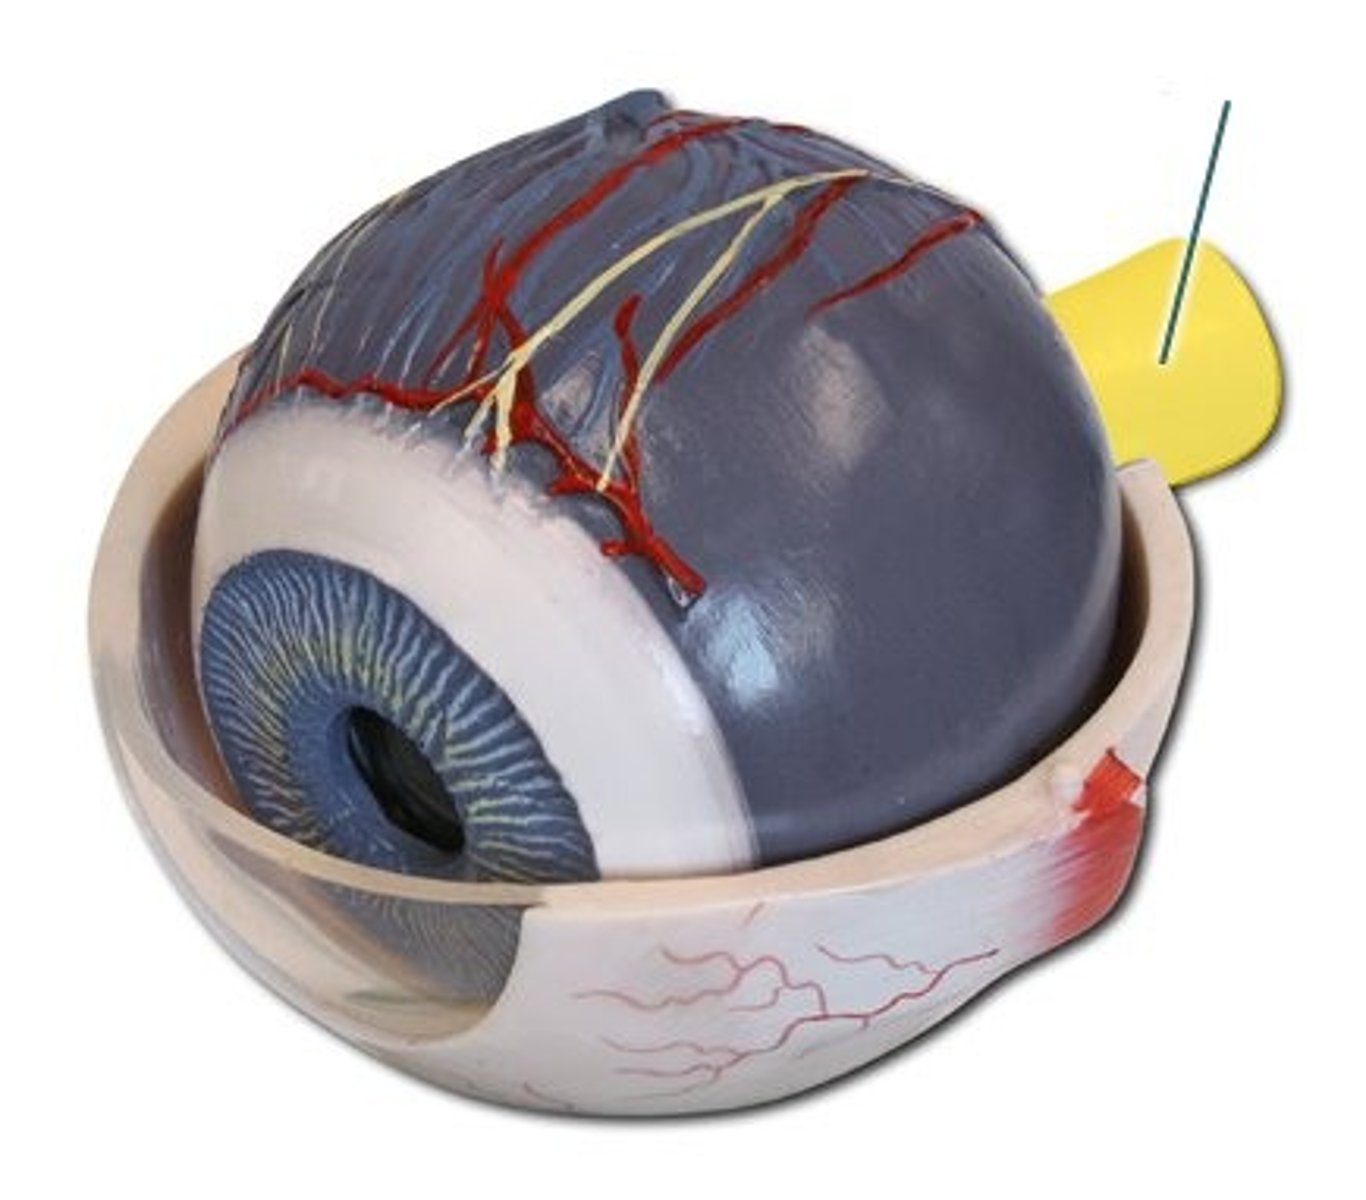

anterior cavity (of eye)

iris

B

optic disk (blind spot)

choroid

L

ciliary body

B

ciliary process

conjunctiva

cornea

D

fovea centralis

suspensory ligaments

C

vitreous humor

lens

H

macula lutea

nasolacrimal duct

lacrimal gland

posterior cavity (of eye)

pupil

F

retina

M

sclera

optic nerve